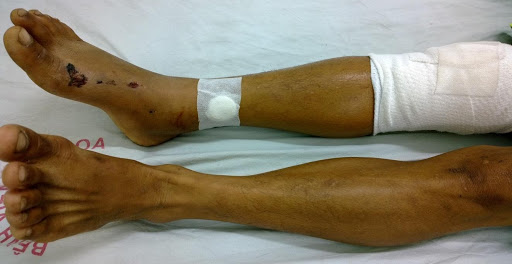

Hình 5: Bệnh nhân được bôi cream LIXU VẠN XUÂN

Hình 7: Can xương của bệnh nhân sau 4 tuần điều trị